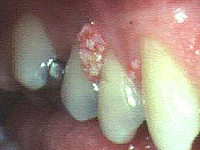

菜花臨床圖片

菜花剛冒出芽時是小小的一點, 漸漸長大後, 就像花椰菜樣的一團, 可能是只長一處, 也可能是好幾叢大小不一的花團

尖形濕疣的潛伏期平均約為三個月左右,甚至更久。再者,其臨床表現多樣化,包括:粉紅色、肉色或污灰色的小丘疹、絲狀樣、乳突瘤樣、雞冠樣、蕈樣或菜花樣突起等。初起不痛、不癢、沒有分泌物,有凸狀膚色或紅色小丘疹,常同時長數個或數個地方,對身體沒有大害,故常被人忽視,而且會慢慢繁衍、增大、變多,各人的體質不同,發病的情形各不同,嚴重長入尿道口,造成尿路阻塞,排尿困難,產生尿道炎、腎臟發炎。